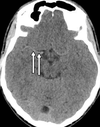

A

venous sinus confluence

aka torcula herophili